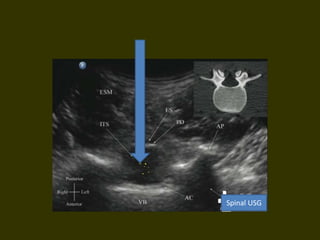

Spinal USG

Needle insertion • Whichspace ? • Midline , hitting bone • Cephalad • Rarely inferior and lateral • Get the mental picture • Midline calcification think paramedian